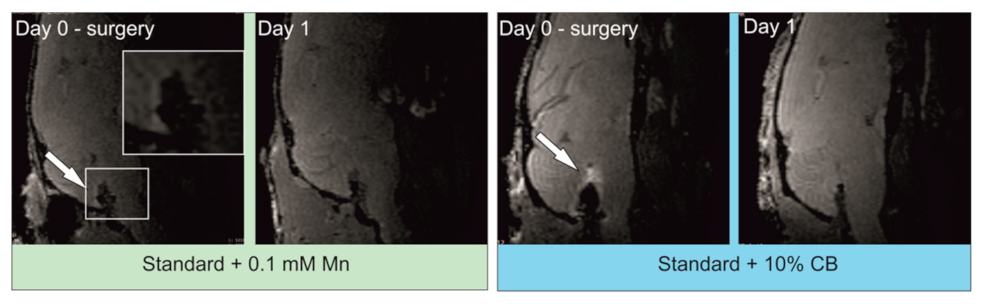

2.5.4. MR Imaging of Intrathecally Transplanted LVM Hydrogels